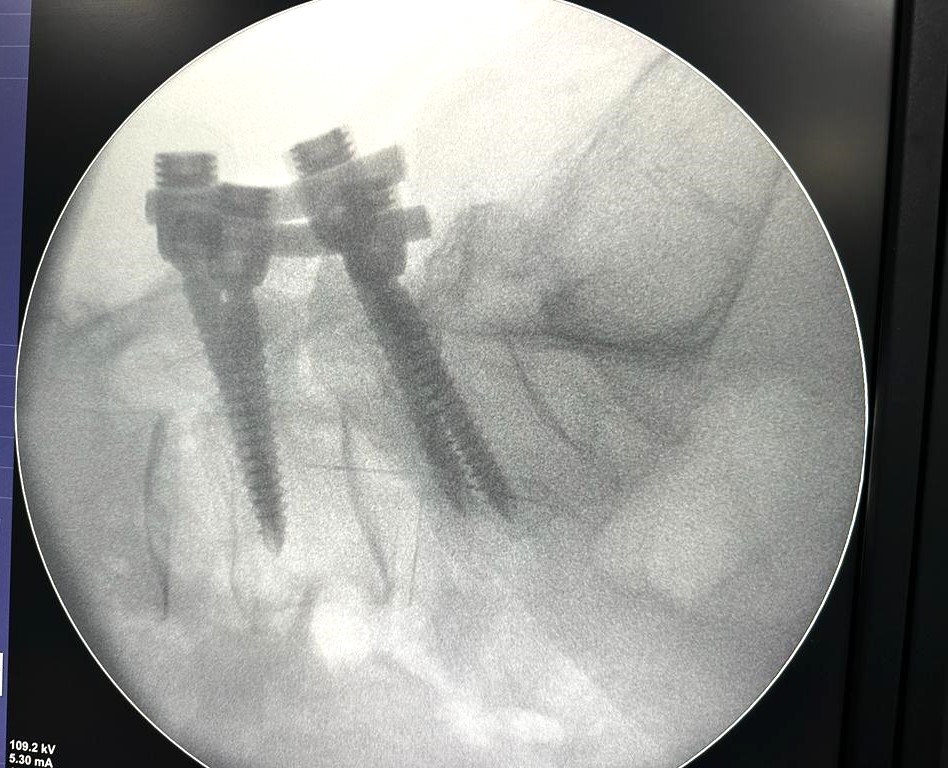

इन्डोस्कोपिक स्पाइन सर्जरी: दुरबीनको मद्दतले ढाडको नसा च्यापिएको शल्यक्रिया हुने क्रम बढेको छ

शुक्रबार, कात्तिक २४, २०८०

मेरूदण्डको ट्युमर कति खतरनाकः संकेत, लक्षण, उपचार र पुनःस्र्थापना

बिहीबार, कात्तिक २३, २०८०

ऐया ! ढाड दुख्यो: नसा च्यापिने कारण र उपचार

बिहीबार, कात्तिक १६, २०८०